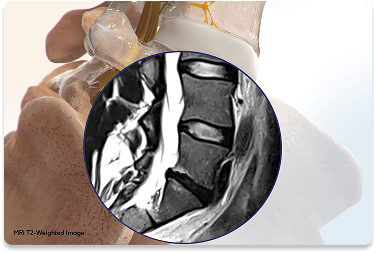

The Intracept® Procedure is a minimally invasive treatment specifically designed for chronic low back pain caused by vertebrogenic pain—a condition linked to damage in the vertebral endplates. These endplates, located between the spinal discs and vertebrae, can become irritated over time, triggering pain signals through a nerve called the basivertebral nerve. Intracept® works by using radiofrequency energy to precisely target and disable the basivertebral nerve, stopping it from sending pain signals to the brain.

Vertebrogenic pain is a specific type of chronic low back pain caused by damage to the vertebral endplates. These thin layers of tissue cover the tops and bottoms of the vertebral bodies and separate them from the intervertebral discs. As discs degenerate with age or everyday stress, the endplates can become damaged and inflamed. This irritation stimulates the basivertebral nerve, which then transmits pain from the spine to the brain.

How Do We Diagnose Vertebrogenic Pain?

Vertebrogenic pain is typically identified by distinctive MRI changes called Modic changes. Modic changes are distinctive signs of inflammation or degeneration seen on standard MRI scans. Patients often report: